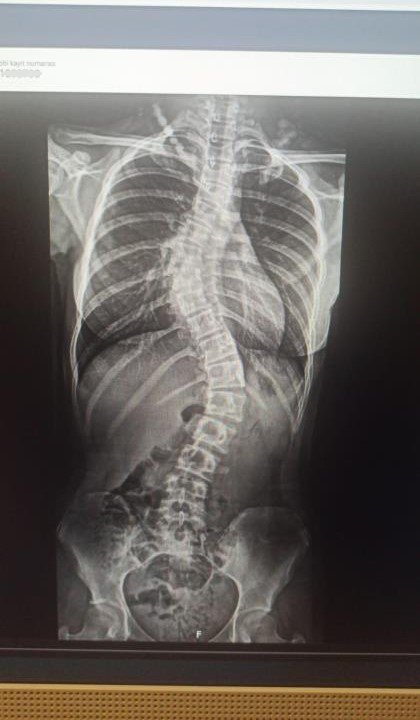

Skolyoz Hastası Zeynep Füzyon Cerrahisi İle Sağlığına Kavuştu

ANTALYA (İHA) – Samsun'da 4 yıldır skolyoz hastası olan 10'uncu sınıf öğrencisi Zeynep Pehlivan'ın sırtında ve belinde bulunan eğrilikler Antalya'da özel bir hastanede gerçekleştirilen füzyon cerrahi tedavisi ile düzeltildi. Ameliyattan bir gün sonra yürümeye başlayan ve 4'üncü günde taburcu edilen Zeynep Pehlivan, "Sağlığıma tekrar kavuştuğum için çok mutluyum" dedi.

Samsun'da yaşayan ve bir süredir skolyoz hastası olan 10'uncu sınıf öğrencisi Zeynep Pehlivan, tedavi için Antalya Memorial Hastanesi Ortopedi ve Travmatoloji Bölümünden Doç. Dr. Ömer Bozduman'a ulaştı. Yapılan görüşmelerin ardından Pehlivan ve ailesi Antalya'ya davet edildi. 4 gün önce Antalya'ya gelen Zeynep Pehlivan için ameliyat kararı alındı. Ameliyatla genç kızın sırtında ve belinde bulunan eğrilikler enstrümantasyonlu bir sistemle füzyon cerrahi tedavisi yaparak düzeltildi. Ameliyatın hemen ardından bir gün sonra yürümeye başlayan Pehlivan, 4 gün sonra taburcu edildi.

Zeynep'in skolyoz hastalığından dolayı uzun zamandır takiplerinde olduğunu belirten Doç. Dr. Ömer Bozduman, "Rahatsızlığı gerilemek yerine ilerleme olunca müdahale etmeye karar verdik. Ameliyatını gerçekleştirdik. Sırtında ve belinde olan eğriliklerini enstrümantasyonlu bir sistemle füzyon cerrahi tedavisi yaparak düzelttik. Ameliyattan sonra birinci gün yürüttük. Problem yaşamadık, dördüncü gün taburcu edeceğiz. Zeynep'in en sık hareketlenmelerinin olduğu boyun sırt bileşkesine beliyle kalça bileşkesine dokunmadık. Daha az hareketsiz olan sırt bölgesine füzyon cerrahi yaptık. Bundan sonra çok fazla bir fonksiyon kaybı olacağını düşünmüyoruz" dedi.